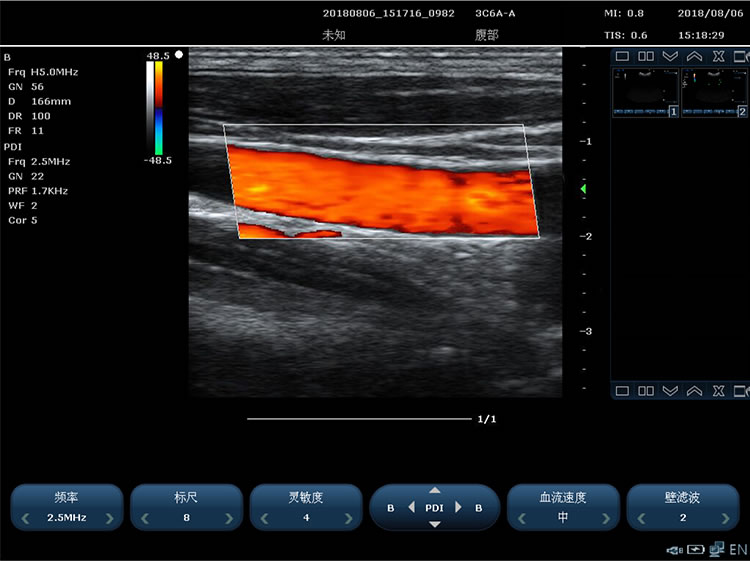

Color Doppler technique requirements:

1)The doppler gain is continuously adjustable

2)Color enhancement

3)B+COLOR display on both left and right sides of the same screen

4)Color mode baseline adjustment ±15 grades